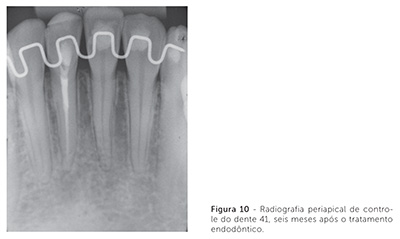

A radiografia panorâmica final mostra o paralelismo radicular obtido e, nas radiografias periapicais, pode-se visualizar a ausência de reabsorções radiculares (Fig. 9). Durante o tratamento, sugeriu-se aos pais que o dente 41 fosse restaurado. Contudo, o clínico odontológico geral solicitou que se aguardasse até o final do tratamento para realizar esse procedimento. Ao final, o dente 41 apresentou rarefação apical, conforme se observa na radiografia periapical final. A paciente foi indicada ao profissional competente para o tratamento endodôntico e restauração desse dente, os quais foram realizados um mês após a remoção da aparelhagem ortodôntic. Em controle radiográfico após seis meses, esse dente apresentava reparo periapical (Fig. 10).